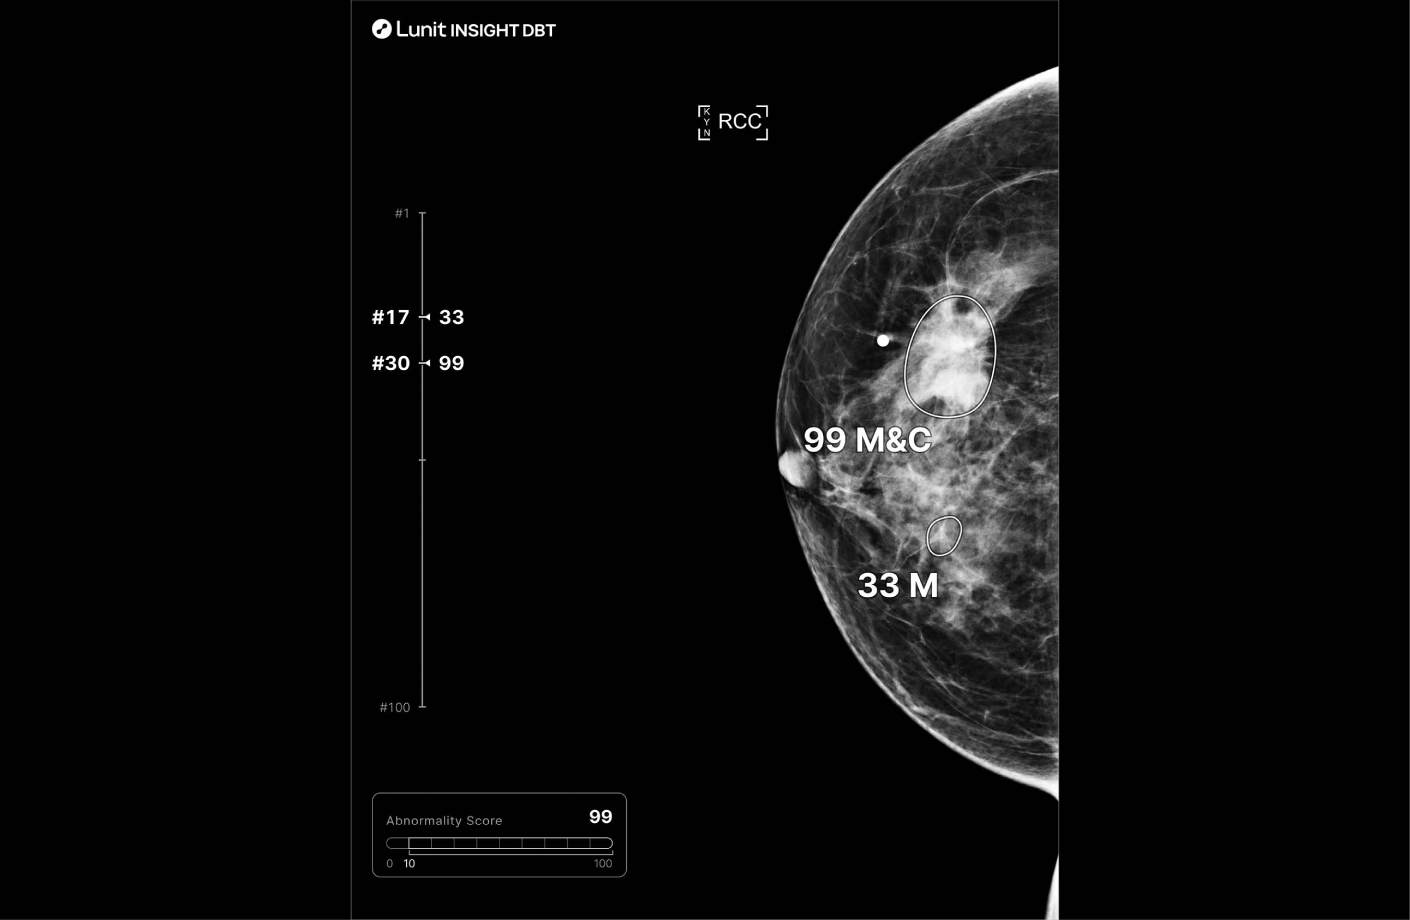

Each suspicious lesion is assigned an abnormality score (0–100), helping quantify malignancy likelihood. Location is clearly marked using heatmaps or contours, and lesion types—such as masses (including architectural distortion and asymmetry), and calcifications—are identified for targeted interpretation. The best slice for lesion visualization is marked on the navigation bar for quick review.